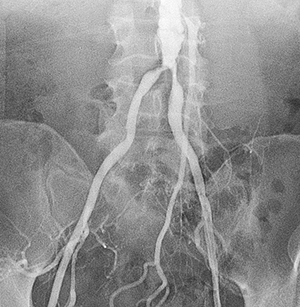

Peripheral Angiography

Peripheral angiography is a test that uses X-ray and dye (contrast material) to map the blood vessels (arteries) in your lower body, legs, and arms. This map can show where blood flow may be blocked.

Contrast dye is injected into the catheter to confirm position. You may feel warmth or pressure in your legs and back. You lie still as X-rays are taken. The catheter is then taken out.